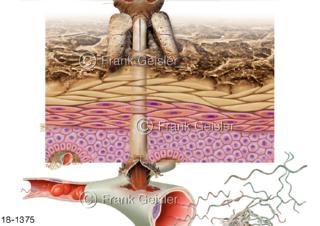

18-1375 Notfall Borreliose-Infektion durch Zeckenbiss Borrelien Borrelia burgdorferi